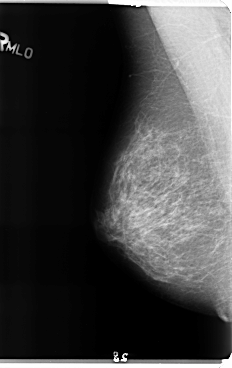

B_3158_1.LEFT_MLO

LEFT_MLO LINES 4760 PIXELS_PER_LINE 2760 BITS_PER_PIXEL 12 RESOLUTION 50 OVERLAY

RIGHT_MLO LINES 4776 PIXELS_PER_LINE 3008 BITS_PER_PIXEL 12 RESOLUTION 50 NON_OVERLAY